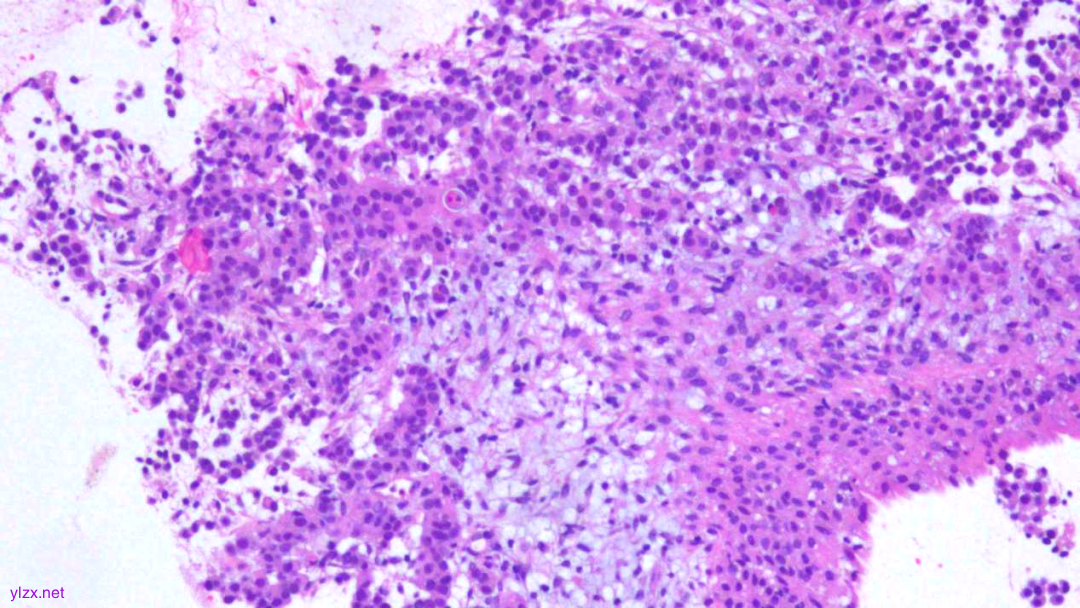

HE:

黏膜间质内见胞浆丰富,红染及粉染瘤细胞弥漫分布,部分细胞核稍偏位,核圆形,稍增大,深染,见核仁,穿插在固有腺之间,伴少量炎细胞浸润。

瘤组织穿插在固有腺之间,较弥漫,核稍增大,深染

瘤细胞稀疏排列,胞浆粉染及红染,宽阔

瘤细胞核圆形,见核仁,部分细胞核偏位,未见核分裂象

瘤细胞核仁明显